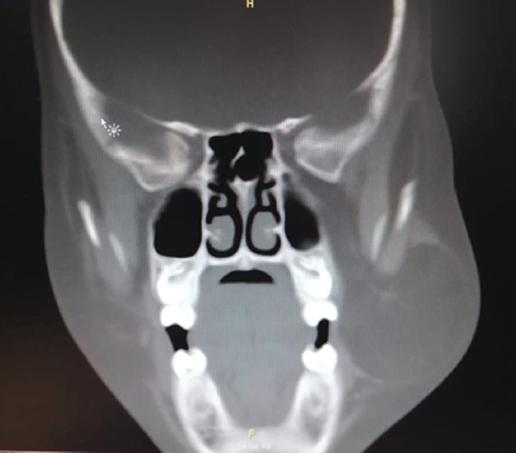

La tomografía computarizada simple de cabeza y cuello evidenció asimetría de la hemicara izquierda a expensas de tejidos blandos, correspondiente a una masa delimitada por una cápsula inmediatamente debajo del músculo buccinador, con una atenuación de −99 UH correspondiente a densidad de tejido graso. Sus límites abarcaban anteriormente hasta el músculo depresor del ángulo de la boca, interiormente el borde inferior de la mandíbula, lateralmente se ubicaba sobre el músculo masetero, extendiéndose anteriormente hasta el arco cigomático. Se observa una ramificación hacia la fosa infratemporal, rodeando el músculo pterigoideo lateral. Sus diámetros máximos eran de 53 × 44 × 46 mm (Fig. 2).

Figura 2 Tomografía computarizada simple, corte coronal. Se observa la extensión infratemporal del lipoma.